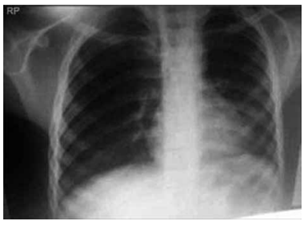

Leia o caso clínico a seguir para responder à questão:

Paciente de 67 anos, tabagista 40 maços/ano, ex-

-fumante há 3 anos, diagnosticado com doença pulmonar

obstrutiva crônica (DPOC), classificado como GOLD D

há 4 anos (VEF₁: 38% do previsto). Faz uso de tiotrópio e

formoterol regularmente, sem oxigenoterapia domiciliar.

Chega ao pronto atendimento com dispneia intensa e

aumento de volume de escarro purulento há 3 dias, evoluindo com cansaço progressivo e confusão mental nas

últimas horas.

Ao exame físico: FR: 28 irpm, uso de musculatura acessória SatO₂: 82% em ar ambiente.

PA: 138 × 86 mmHg; FC: 112 bpm; T: 37,8 °C.

Ausculta pulmonar com roncos difusos e sibilos esparsos.

Gasometria arterial pH: 7,28; PaCO₂: 68 mmHg; PaO₂:

54 mmHg; HCO₃⁻: 31 mEq/L.

Radiografia de tórax a seguir:

(Arquivo pessoal; imagem usada com autorização)